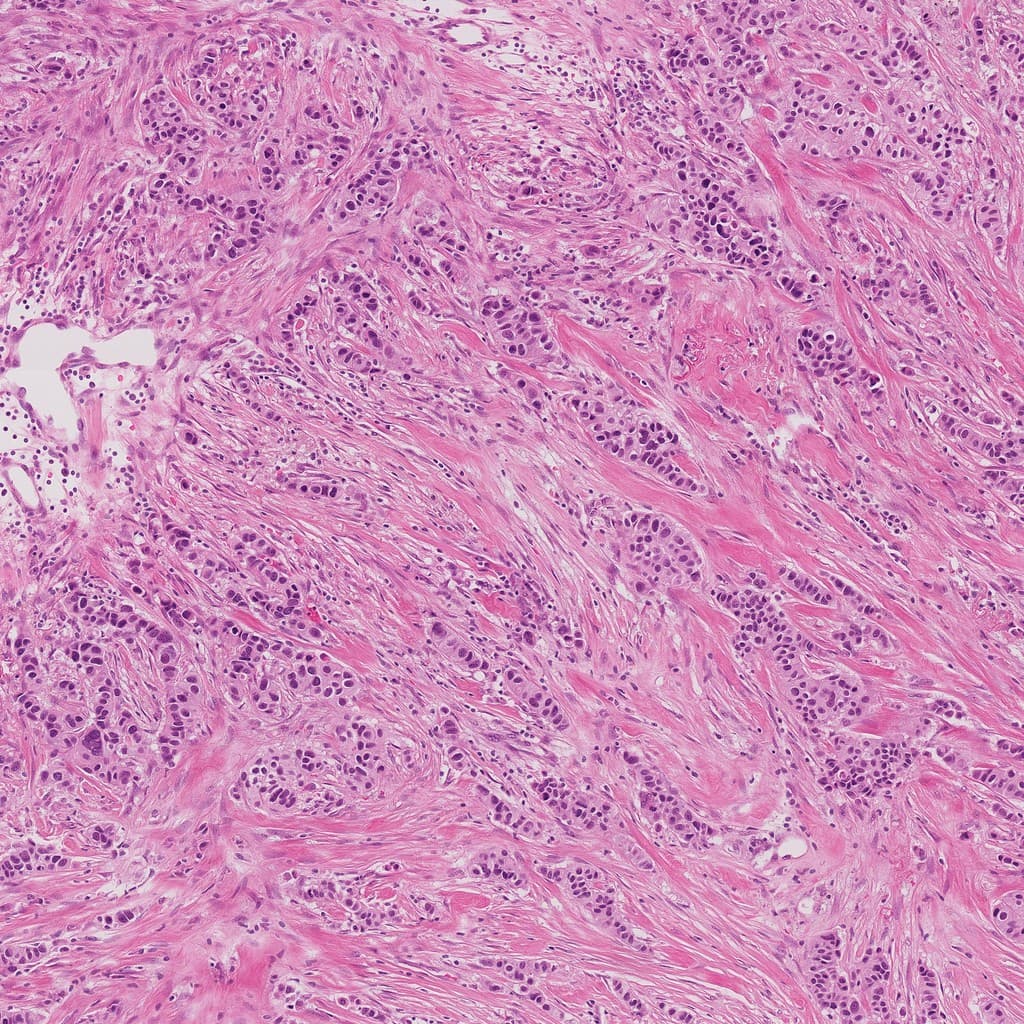

Dark purple solid area with significantly increased cell density and locally back-to-back arrangement suggests suspicious neoplastic lesion.

At 10× magnification, dysplastic glands show complex distribution suggesting stromal invasion. Dense cellularity without diffuse necrosis or hemorrhage. Mild stromal inflammatory infiltration, no significant carbon deposition or pseudodense areas from alveolar collapse, excluding non-neoplastic dense shadows.

Tumor cells infiltrate in acinar and papillary patterns with irregular lumina, partially in back-to-back arrangement. Nuclei are hyperchromatic and variably sized with visible nucleoli and eosinophilic cytoplasm. Stromal fibrosis present without keratin pearl formation or perivascular cuffing. Cell adhesion preserved with some desquamation.